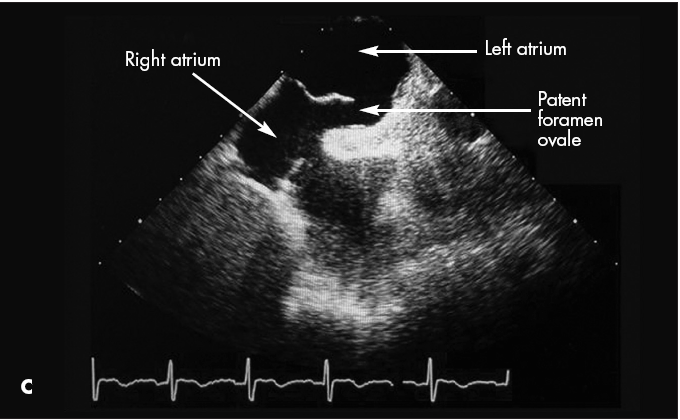

CT scans showed both a pulmonary embolus (A) and a thrombus in the wall of the abdominal aorta (B). Anticoagulation therapy was initiated. A Doppler study showed a left lower extremity deep venous thrombus. Further evaluation with transesophageal echocardiography showed a patent foramen ovale (C) and an interatrial aneurysm, with a positive bubble study.* The patient had no known history of either condition. Because of the patent foramen ovale, thrombi had traveled not only to the lungs but also to the aorta. This likely caused the spinal ischemia and paraparesis.